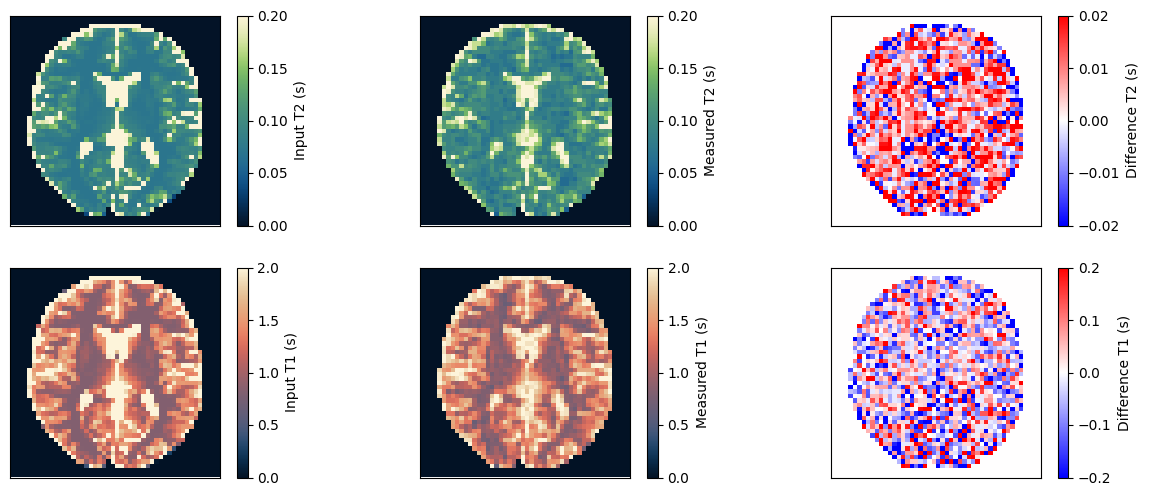

Estimate the T1 and T2 maps#

We use a dictionary matching approach to estimate the T1 and T2 maps. Afterward, we compare them to the input and ensure they match.

fig, ax = plt.subplots(2, 3, figsize=(15, 6))

im = ax[0, 0].imshow(t2_input, vmin=0, vmax=0.2, cmap=Colormap('navia').to_mpl())

fig.colorbar(im, ax=ax[0, 0], label='Input T2 (s)')

im = ax[0, 1].imshow(t2_measured, vmin=0, vmax=0.2, cmap=Colormap('navia').to_mpl())

fig.colorbar(im, ax=ax[0, 1], label='Measured T2 (s)')

im = ax[0, 2].imshow(t2_measured - t2_input, vmin=-0.02, vmax=0.02, cmap='bwr')

fig.colorbar(im, ax=ax[0, 2], label='Difference T2 (s)')

im = ax[1, 0].imshow(t1_input, vmin=0, vmax=2, cmap=Colormap('lipari').to_mpl())

fig.colorbar(im, ax=ax[1, 0], label='Input T1 (s)')

im = ax[1, 1].imshow(t1_measured, vmin=0, vmax=2, cmap=Colormap('lipari').to_mpl())

fig.colorbar(im, ax=ax[1, 1], label='Measured T1 (s)')

im = ax[1, 2].imshow(t1_measured - t1_input, vmin=-0.2, vmax=0.2, cmap='bwr')

fig.colorbar(im, ax=ax[1, 2], label='Difference T1 (s)')

relative_error_t2 = np.sum(np.abs(t2_input - t2_measured)) / np.sum(np.abs(t2_input))

relative_error_t1 = np.sum(np.abs(t1_input - t1_measured)) / np.sum(np.abs(t1_input))

print(f'Relative error for T2: {relative_error_t2} and for T1: {relative_error_t1}')

assert relative_error_t2 < 0.15

assert relative_error_t1 < 0.08

Relative error for T2: 0.1310950368642807 and for T1: 0.07769713550806046